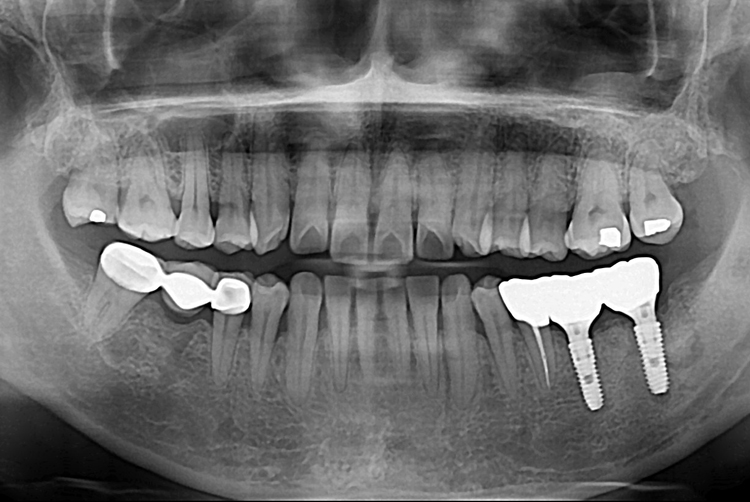

[임플란트] 어금니 임플란트

치료전 : 2019-06-12

세종치과는 많은 환자와 다양한 케이스를 바탕으로

항상 편안한 임플란트 수술을 제공하고자 노력하고,

오래동안 튼튼히 쓸 수 있는 임플란트 수술을 가장 큰 목표로 삼고 있습니다.